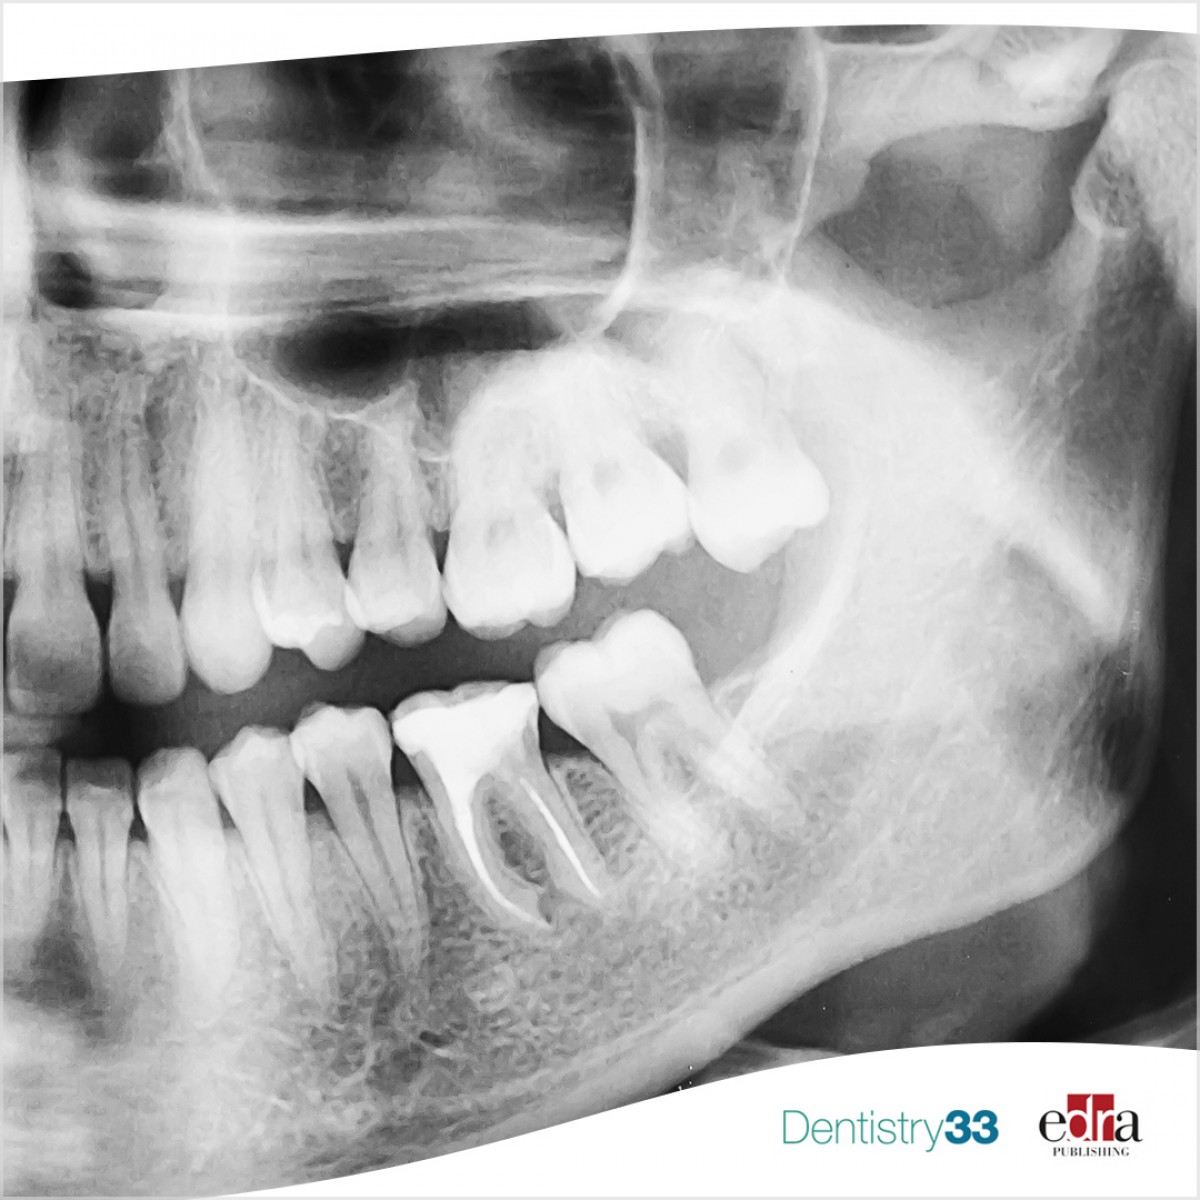

A patient presented after unsuccessful root canal treatment with a ledge on the left mandibular first molar. A CBCT was taken, and the images imported into a segmentation software (Mimics, Materialise).

The canal was isolated, and segmentation performed along with the other structures of the tooth. A 3D representation of the canal and the internal structures of the canal were exported from the software and additively manufactured.

This was used as a pre-clinical guide to simulate the procedure, pre-curve the file and manage the canal.

This novel technique using virtual modelling from CBCT data post ledge formation allowed for successful and quick management of a tooth with ledges.